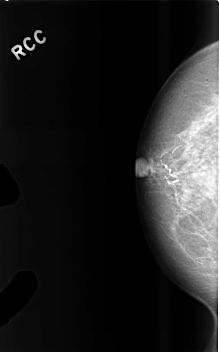

Digital Database for Screening Mammography

Volume: benign_14 Case: C-0476-1

C_0476_1.RIGHT_CC

RIGHT_CC LINES 4568 PIXELS_PER_LINE 2856 BITS_PER_PIXEL 12 RESOLUTION 50 NON_OVERLAY